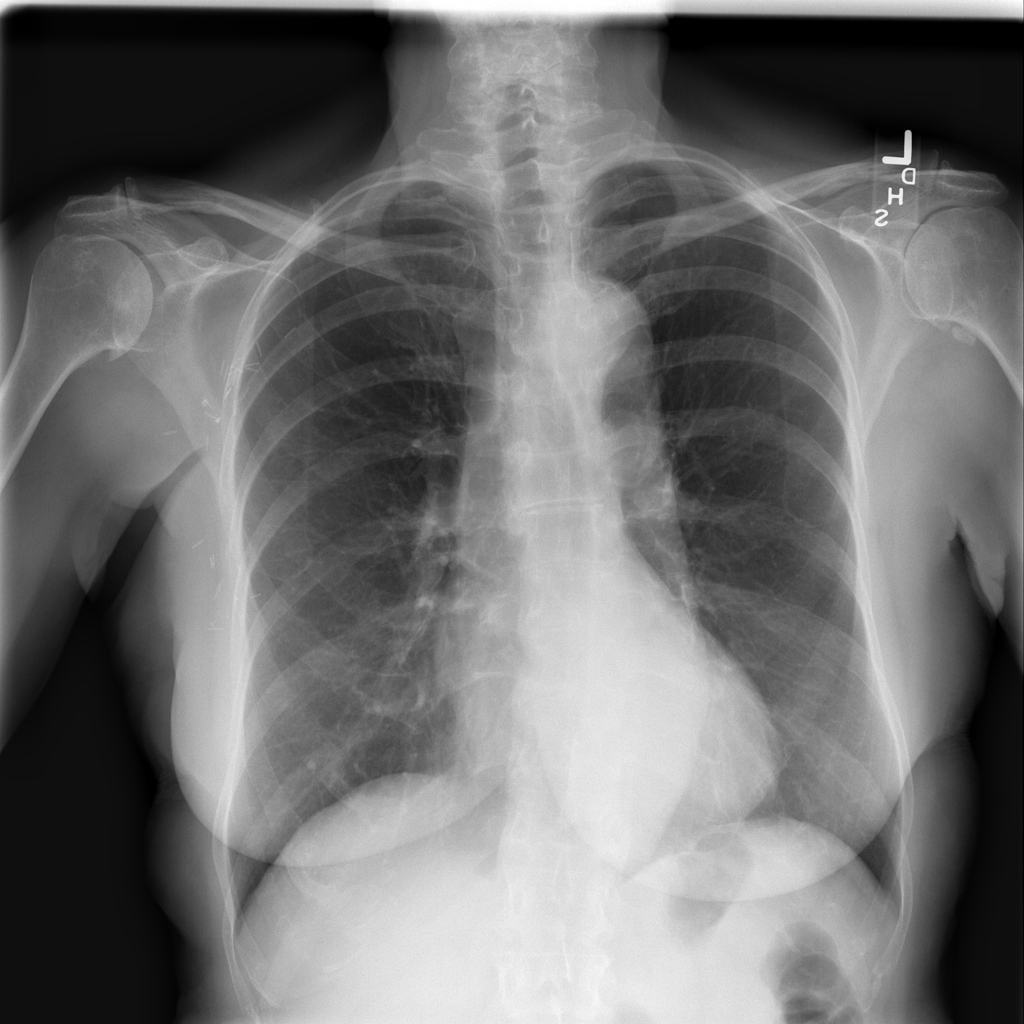

Showing up to 90 reference images for Emphysema.

PAT-B0DB · IMG-003Emphysema

PAT-B0DB · IMG-003

PA